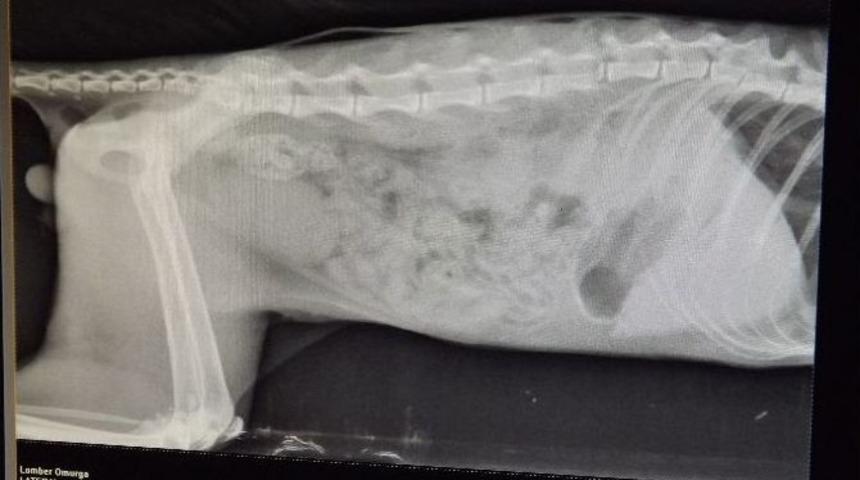

Araba çarpması sonucu beli kırılan kedi, Osmangazi Belediyesi Sahipsiz Hayvanlar Doğal Yaşam ve Tedavi Merkezi’nde hayata tutundu.Hamitler Mahallesi’nde araba çarpması sonucu ağır yaralı halde vatandaşlar tarafından bulunan kedi, Osmangazi Belediyesi Sahipsiz Hayvanlar Doğal Yaşam ve Tedavi Merkezi’ne getirildi. Sahip olduğu teknik ve fiziki imkanlar bakımından Avrupa’nın en büyük ve en donanımlı merkezlerinin başında gelen Osmangazi Belediyesi Sahipsiz Hayvanlar Doğal Yaşam ve Tedavi Merkezi’nde ilk olarak röntgeni çekilen kedinin belinin kırık olduğu tespit edildi. Yapılan tetkiklerin ardından yaralı kediye hemen müdahalede bulunan barınak yetkilileri, başarılı geçen ameliyatın ardın kediyi yoğun bakıma aldı. Yetkilileri, tedavi süreci devam eden kedinin durumunun iyi olduğunu ve kısa süre içerisinde eski sağlığına kavuşacağını belirtti.Osmangazi Belediye Başkanı Mustafa Dündar, geçtiğimiz yıl 6 bin 114 sokak hayvanına bakım ve sağlık hizmeti veren Osmangazi Belediyesi Sahipsiz Hayvanlar Doğal Yaşam ve Tedavi Merkezinde, binlerce sahipsiz hayvanın sağlığına kavuşarak yaşama yeniden dönme imkanı bulduğunu söyledi. Dündar; “Geçtiğimiz yıl 2 bin 748 hayvanın koruyucu hekimlik hizmetinden faydalandığı merkezde, bin 117 sokak hayvanına tıbbi tedavi yapıldı. Ayrıca, ekiplerimiz tarafından toplanan 2 bin 25 sokak hayvanına kısırlaştırma ameliyatı, 898 sokak hayvanına ise kısırlaştırma harici ameliyat ve konservatif tedavi hizmeti verildi. Vatandaşların bulup barınağa getirdiği kedi de, ekiplerimiz tarafından yapılan müdahalenin ardından kısa sürede sağlığına kavuşacaktır” diye konuştu.